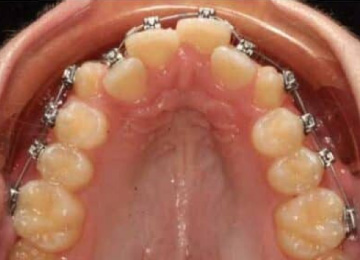

Брекеты: фото До и После

Внешне брекеты выглядят почти одинаковы, однако могут отличаться по способу крепления:

- для лигатурных брекетов характерна фиксация специальным замком на эластичной ортодонтической дуге;